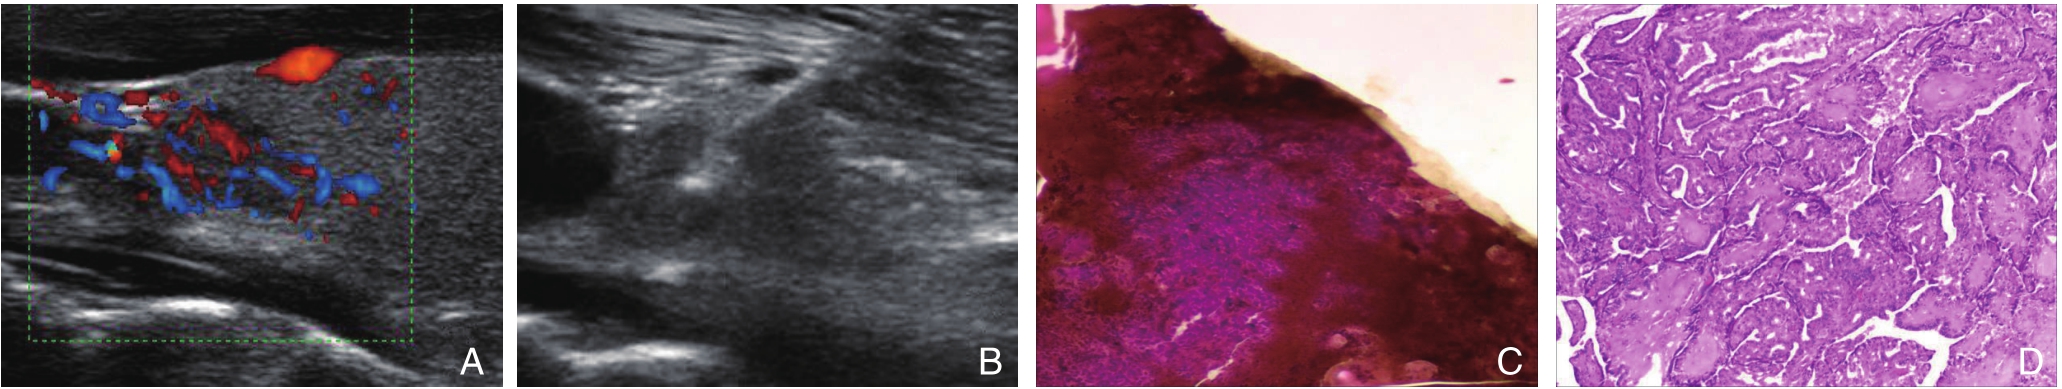

图1 乏血供甲状腺结节 A:CDFI血流Adler I级;B:23G穿刺针行US-FNAB;C:针吸细胞学病理(HE ×200)考虑可疑恶性肿瘤;D:同一患者手术病理诊断甲状腺乳头状癌(HE ×200)

Figure 1 Hypovascular nodule A:Adler's grade I of CDFI;B:US-FNAB performed by 23G needle;C:Suspicious malignancy considered by needle aspiration cytology(HE ×200);D:Papillary thyroid carcinoma diagnosed by postoperative pathology in the same patient(HE×200)